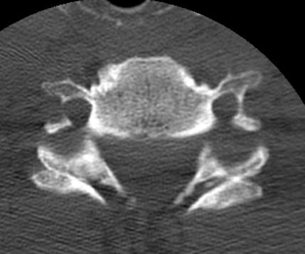

Unilateral facet joint dislocation on CT

>50% forward subluxation

Bilateral jumped facets on CT